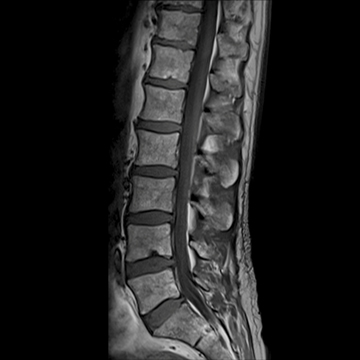

全脊椎

T1 TSE, 448 matrix

T2 STIR, 384 matrix,